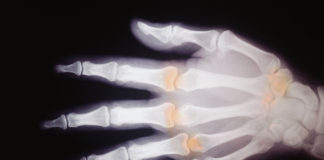

Tag: artrite psoriasica